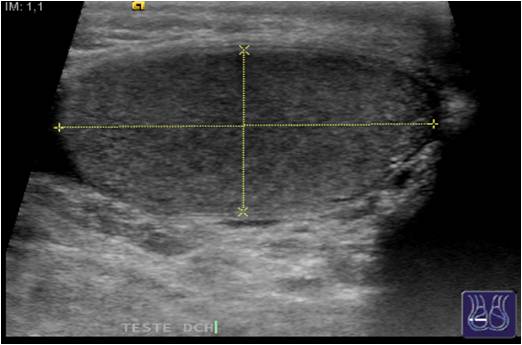

Para estudiar la bolsa escrotal y los Testículos que suelen ser el objetivo principal de este estudio el paciente debe estar en decúbito supino, vamos a pedirle que nos deje el escroto libre de ropa y le pediremos que tire del pene hacia la cabeza del paciente de modo que los testes queden ligeramente inmovilizados.

Usaremos una sonda de alta frecuencia, en torno a los 16 mhz sería ideal, Vamos a realizar cortes longitudinales y transversos de ambos testes con medidas en los tres ejes del espacio.

En longitudinal haremos la medida cráneo-caudal y en transverso haremos medidas antero-poterior y derecha izquierda.

Tanto en un plano como en el otro debemos escoger la parte central de la estructura para que las medidas sean fiables.

Corte Longitudinal y medida.Obsérvese el picto.

El Teste es una estructura oval, homogénea e hiperecogénica.